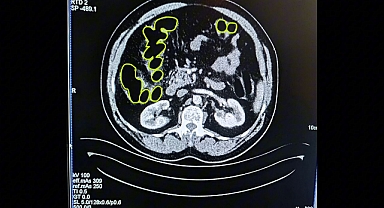

Kayseri İl Jandarma Komutanlığı ekiplerince yapılan çalışmalar neticesinde; İran uyruklu 3 şahsın Kayseri Şehir Hastanesi'nde yapılan iç beden muayenesinde mide ve bağırsaklarında uyuşturucu olduğu değerlendirilen yabancı maddeler tespit edilerek hastanede müşahede altına alınmışlardır. Şahısların midelerinden doğal yollarla çıkan 215 adet kapsül içerisinde 2680 Gram Eroin ve 56 adet kapsül içerisinde 702 Graam Metamfetamin maddesi olmak üzere, toplam 271 kapsül içerisinde 3 kilo 382 Gram uyuşturucu madde ele geçirildi. Şüpheliler Cumhuriyet Savcılığına mevcutlu olarak sevk edildi ve çıkarıldıkları ilgili mahkeme tarafından tutuklanarak Bünyan Kapalı Ceza İnfaz Kurumu'na teslim edildi.